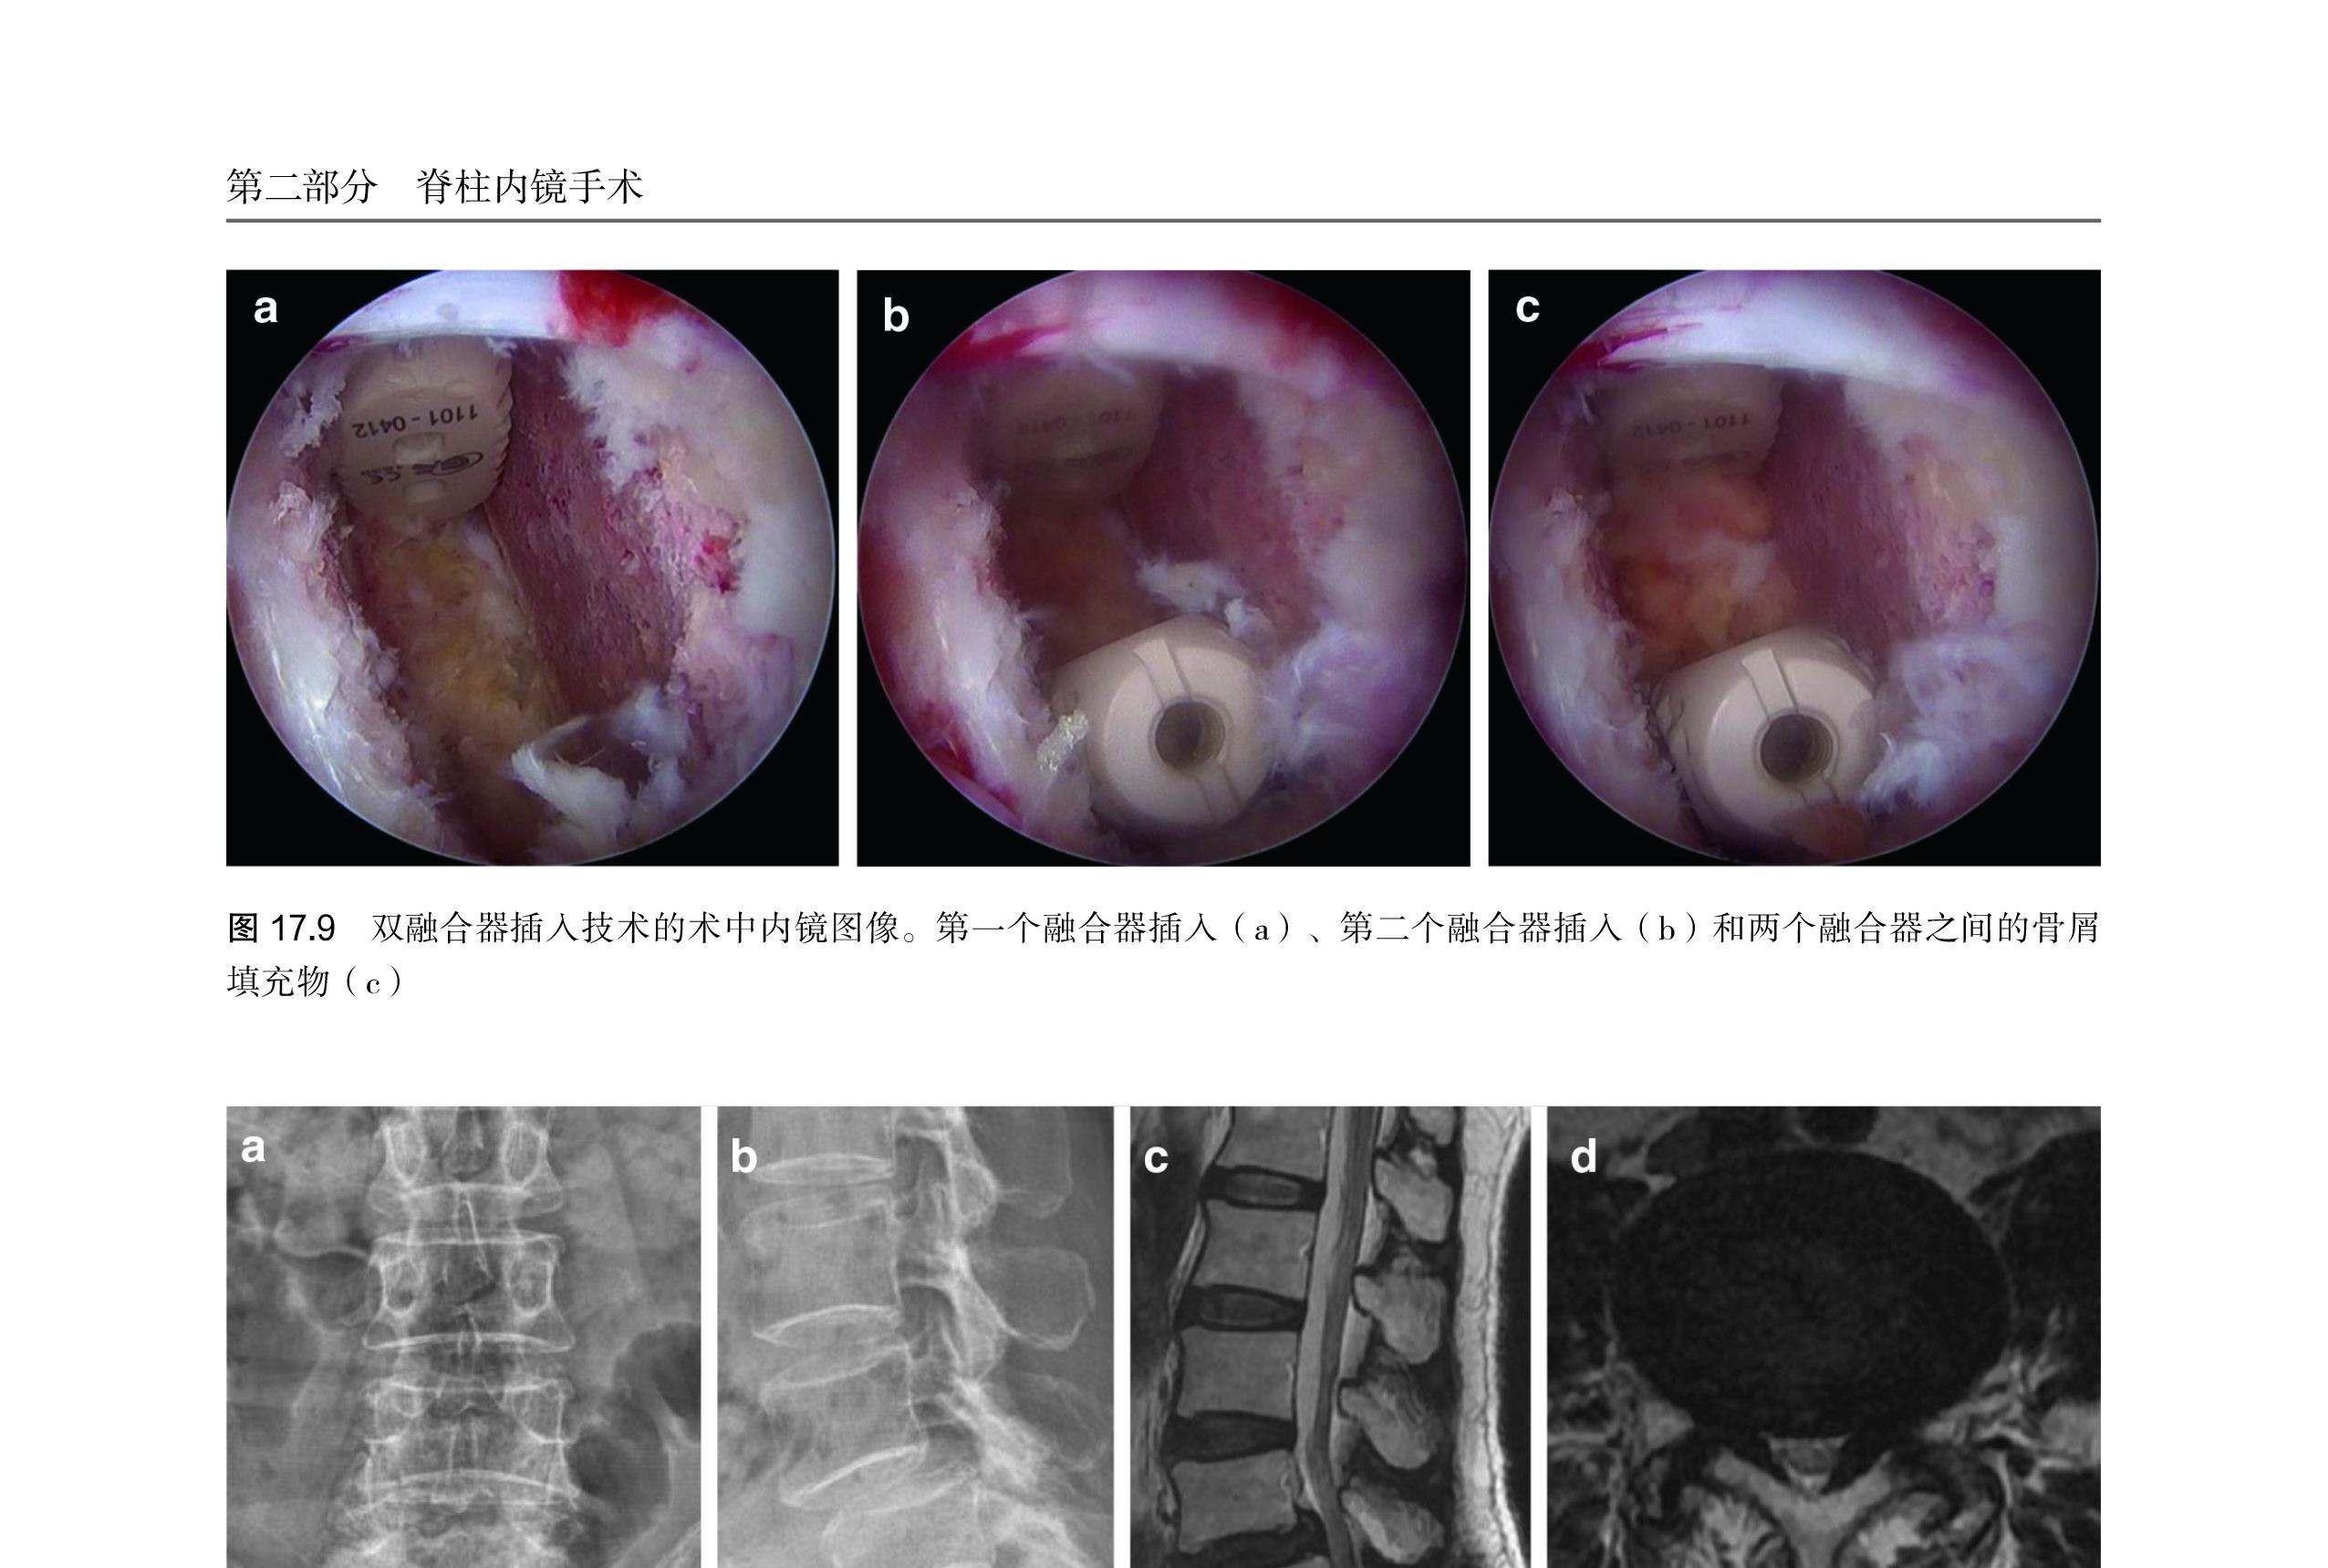

第 17 章 双通道内镜腰椎间融合术 …… 123